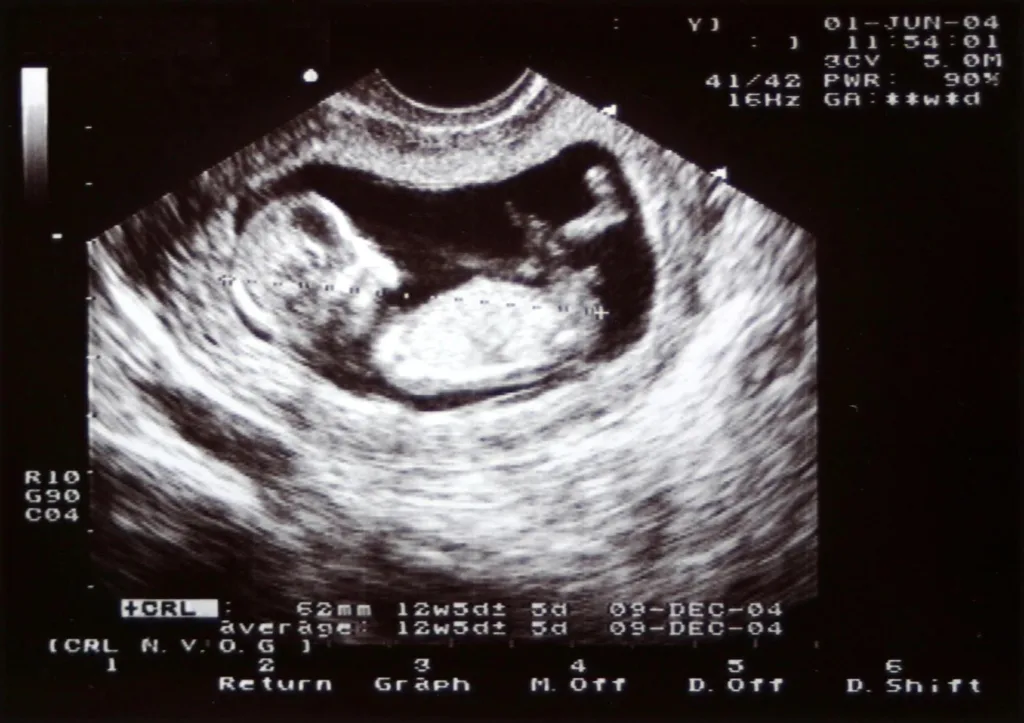

Die Schwangerschaft ist eine aufregende Zeit, gefüllt mit Vorfreude und natürlich auch einigen Ängsten. Ein wichtiger Bestandteil der Schwangerschaftsbetreuung sind die Ultraschalluntersuchungen. Diese dienen nicht nur dazu, das ungeborene Kind zu betrachten, sondern vor allem, um die Gesundheit von Mutter und Kind zu kontrollieren. Der letzte Ultraschall in der Schwangerschaft, der meist zwischen der 3und 3Schwangerschaftswoche stattfindet, spielt dabei eine besonders wichtige Rolle. Er gibt Aufschluss über den Gesundheitszustand des Babys kurz vor der Geburt und hilft, eventuelle Komplikationen frühzeitig zu erkennen.

Der letzte Ultraschall findet meist zwischen der 3und 3Schwangerschaftswoche statt. Der genaue Zeitpunkt kann jedoch je nach Schwangerschaftsverlauf und den Empfehlungen des Arztes oder der Ärztin variieren.